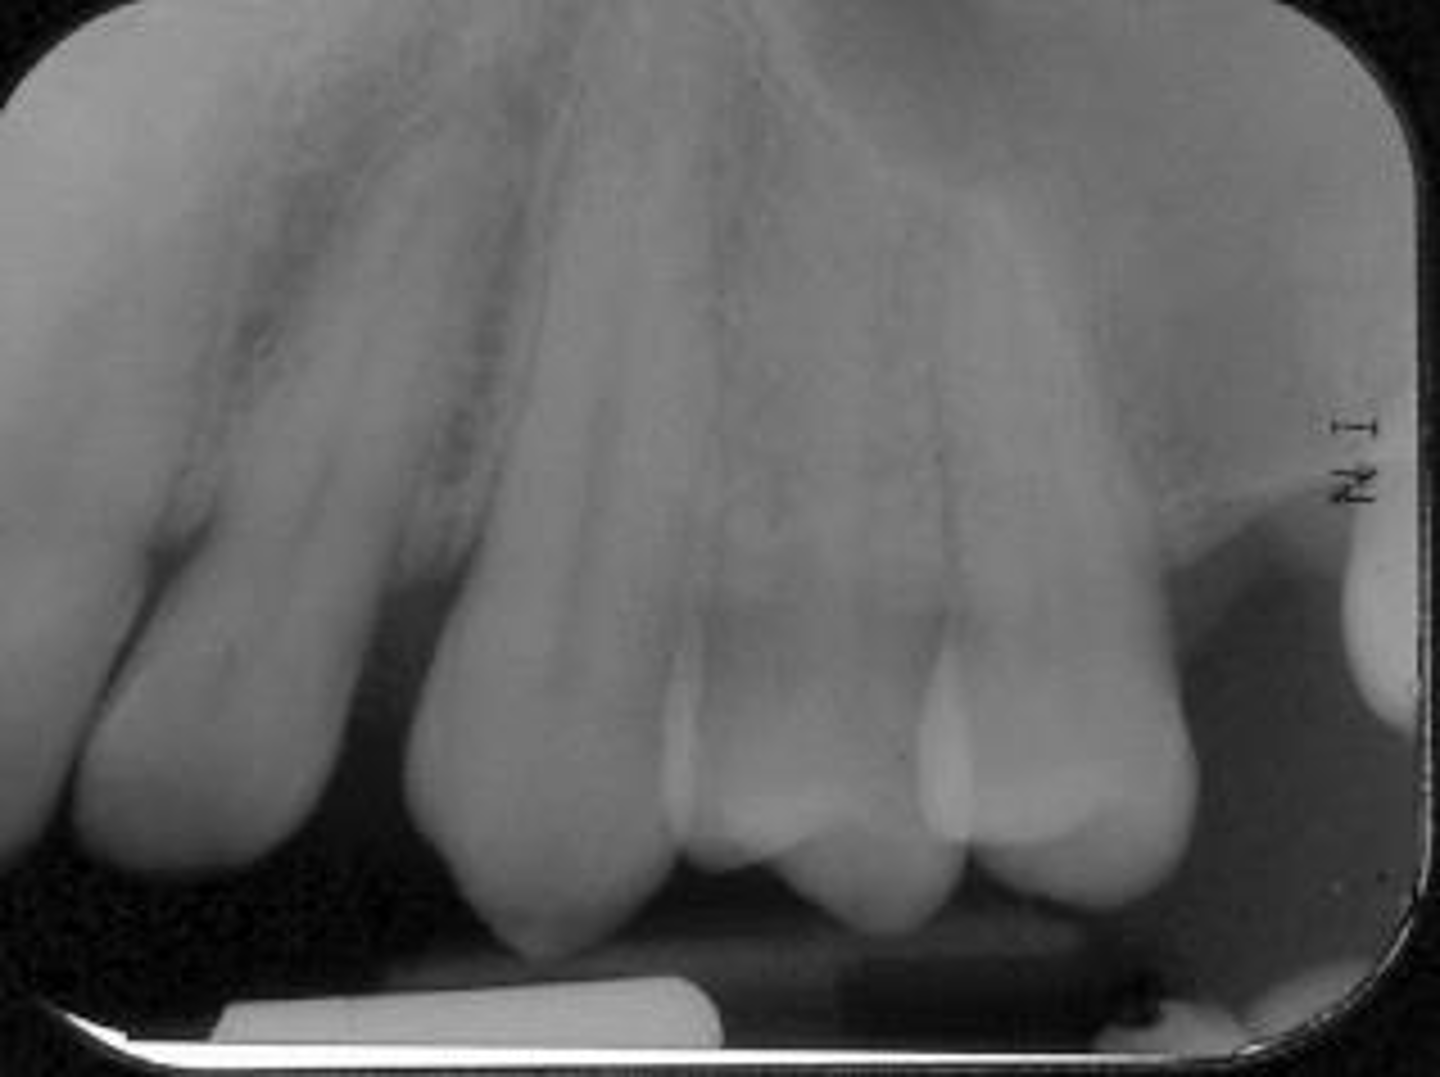

Elongated, vertical angulation, film holder (metal bar)

What is this error?